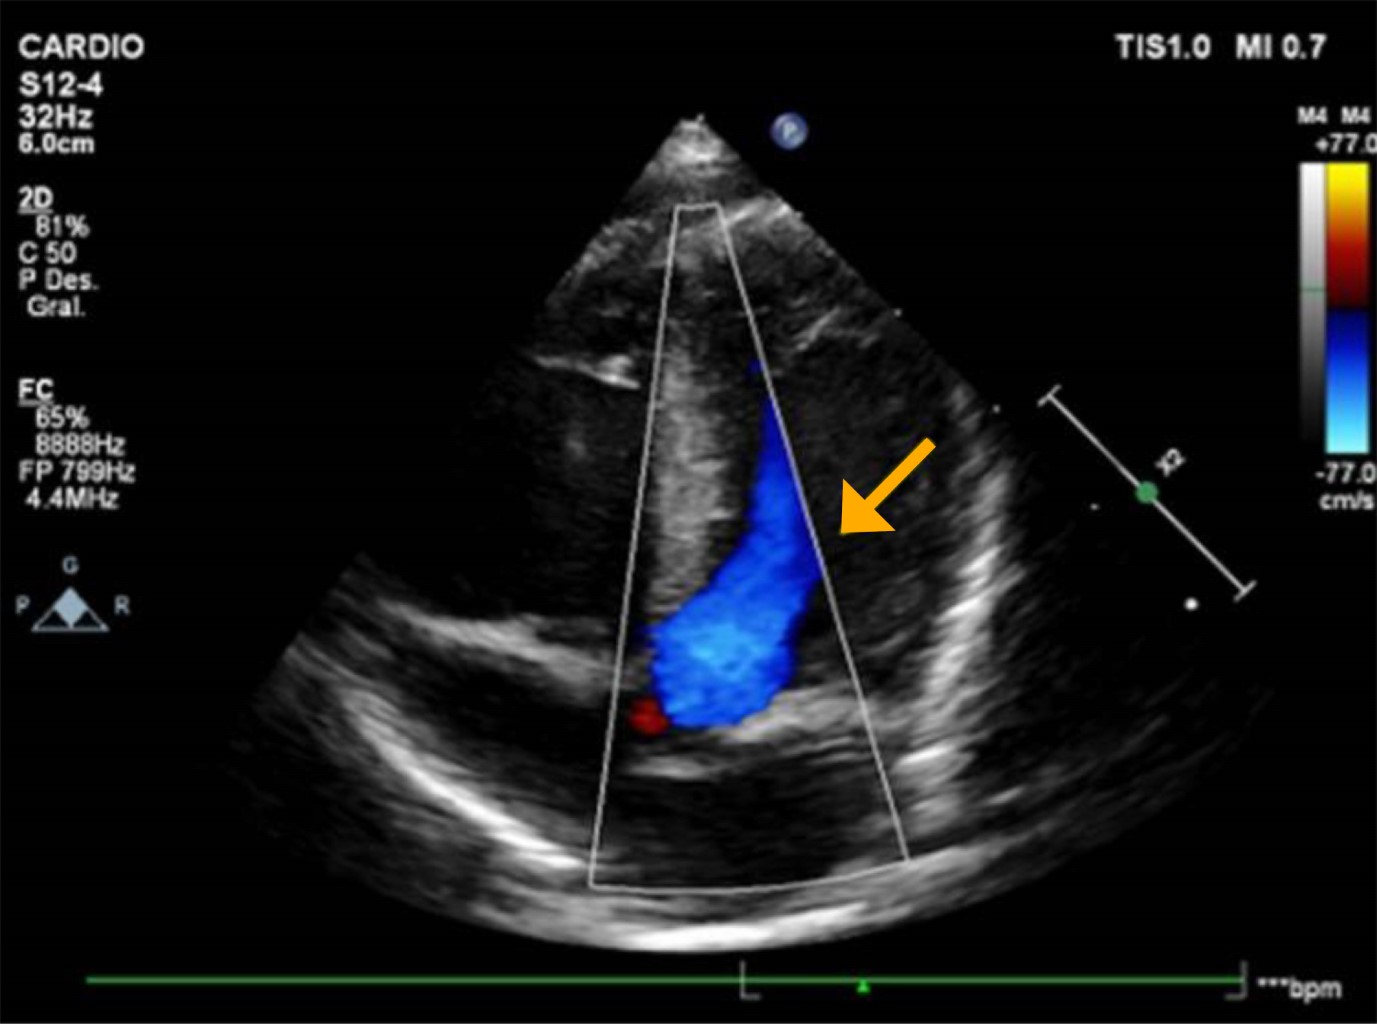

Ante datos sugestivos de miocardiopatía se realizó ecocardiograma transtorácico, que mostró aumento de grosor miocárdico en ventrículo izquierdo, de predominio septal que se consideró grave (tabique interventricular 7.8 mm, z-score +4 para peso y talla). No se evidenciaron datos de obstrucción intraventricular, mientras que la función y contractilidad ventricular estaban conservadas. Se diagnosticó miocardiopatía hipertrófica asimétrica septal no obstructiva (Figuras 3 y 4).

Figura 3